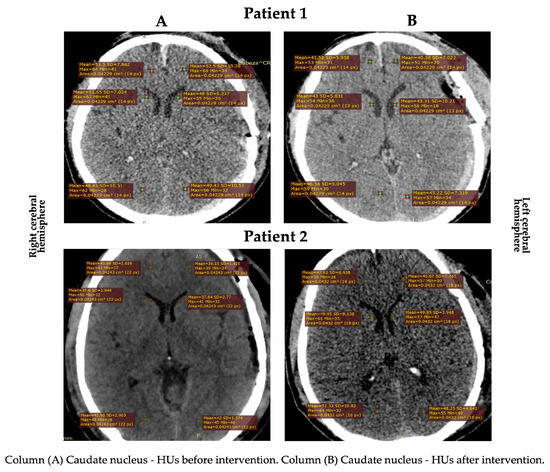

| Before | After | Difference (%) | |

|---|---|---|---|

| RCH | |||

| TR (HU) | |||

| Patient 1 | 47.39 | 41.72 | 05.67 (↓ 11.96) |

| Patient 2 | 65.41 | 54.19 | 11.22 (↓ 17.15) |

| CN (HU) | |||

| Patient 1 | 51.65 | 43.00 | 08.65 (↓ 16.74) |

| Patient 2 | 35.60 | 49.95 | 14.35 (↑ 28.72) |

| LCH | |||

| Patient 1 | 55.79 | 47.43 | 08.36 (↓ 14.98) |

| Patient 2 | 41.72 | 50.50 | 08.78 (↑ 17.38) |

| Patient 1 | 48.00 | 43.31 | 04.90 (↓ 09.77) |

| Patient 2 | 37.64 | 49.95 | 12.31 (↑ 24.64) |